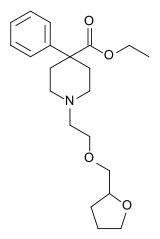

The first fully synthetic opioid was meperidine (later demerol), found serendipitously by German chemist Otto Eisleb (or Eislib) at IG Farben in 1932.[228] Meperidine was the first opiate to have a structure unrelated to morphine, but with opiate-like properties.[199] Its analgesic effects were discovered by Otto Schaumann in 1939.[228] Gustav Ehrhart and Max Bockmühl, also at IG Farben, built on the work of Eisleb and Schaumann. They developed "Hoechst 10820" (later methadone) around 1937.[230] In 1959 the Belgian physician Paul Janssen developed fentanyl, a synthetic drug with 30 to 50 times the potency of heroin.[211][231] Nearly 150 synthetic opioids are now known.[228]